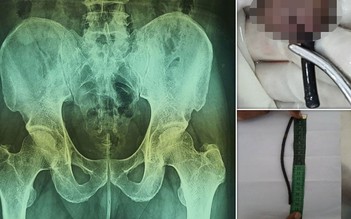

Người đàn ông nhập viện vì nhét sợi dây vào 'của quý' để dễ đi tiểu